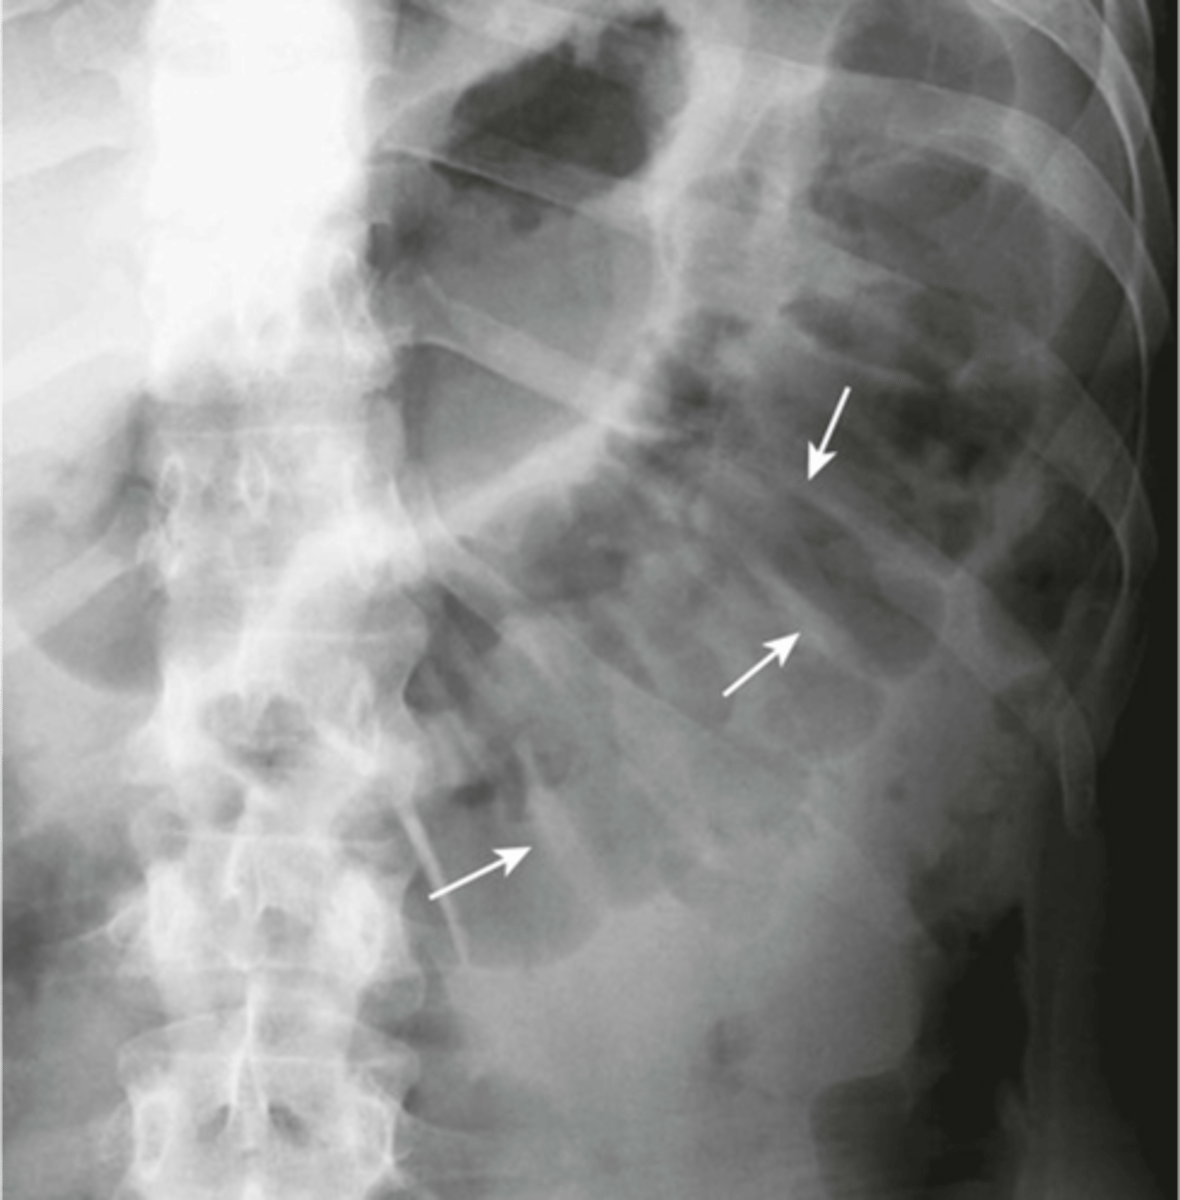

free air (pic 1)

Free air (pic 2)

free air under the diaphragm (indicative of pneumoperitoneum)